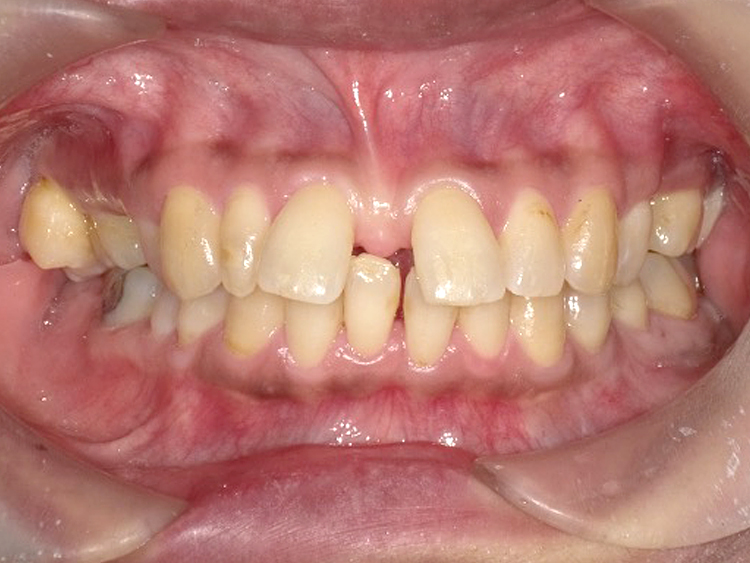

症例4

Before

After

| 主訴 | 上下前歯のがたつき |

|---|---|

| 年齢 | --- |

| 治療 期間 |

約9ヶ月 |

| 治療 内容 |

インビザラインiGoで上下顎の治療。 |

| 治療費 | ¥550,000(税込)/調整料含む |

| 治療のリスク | 矯正終了後は、リテーナーを指示通りに使用し、歯の後戻りを防ぐ必要があります。 |